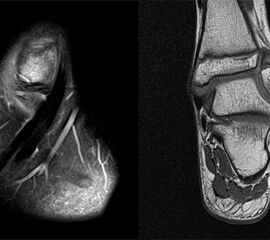

Osteochondrale Verletzungen

Osteochondrale Verletzungen können infolge eines Distorsionstraumas beobachtet werden (Taluskantenfraktur), teilweise lässt sich auch kein Trauma eruieren. Der es sich bei osteochondralen Verletzungen um keine Arthrose handelt, ist gerade bei Schmerzfreiheit ein defensives Vorgehen angezeigt. Bei offenen Wachstumsfugen kann eine osteochondrale Verletzung unter konservativer Therapie ausheilen.

Eine retrograde Anbohrung ist indiziert, wenn sich im MRT Verlauf eine zunehmende Sklerosierung im Randbereich der Läsion zeigt bei intakter Knorpeloberfläche.

Instabile Knorpelareale werden arthroskopisch entfernt in Verbindung mit einer Mikrofrakturierung der subchondralen Knochenlamelle.